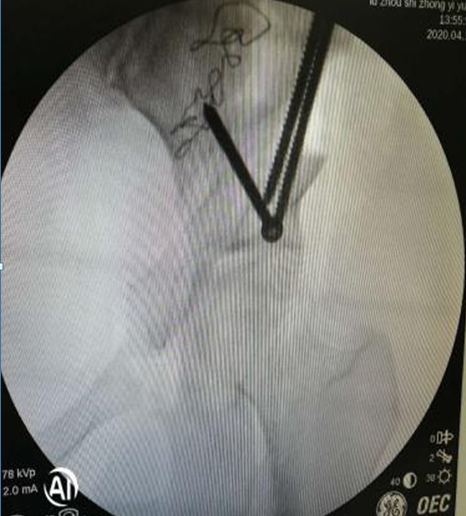

術(shù)中,左側(cè)髖臼周圍截骨

在李彬主任的帶領(lǐng)下,肖女士進行了髖臼周圍截骨術(shù)PAO保髖治療:調(diào)整髖臼位置,使髖關(guān)節(jié)的旋轉(zhuǎn)中心適度內(nèi)移;增加髖臼對股骨頭的覆蓋,增加負重的關(guān)節(jié)面,降低了髖關(guān)節(jié)負重面軟骨的應力,達到了延遲或阻斷髖關(guān)節(jié)炎進展的目的,延長了自身髖關(guān)節(jié)的使用壽命。目前,患者恢復良好。